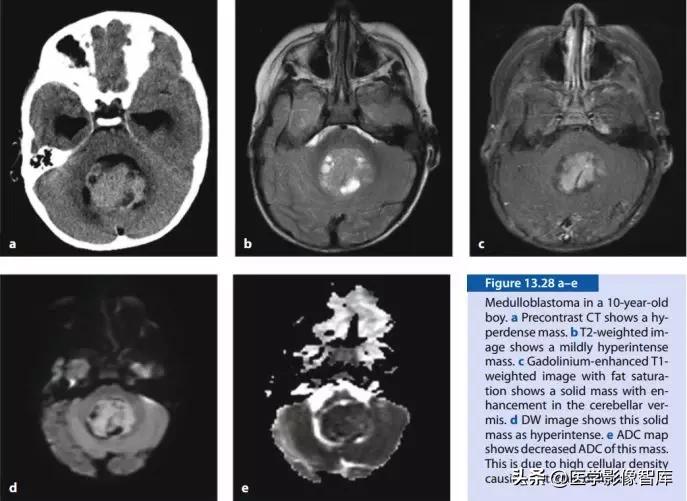

图12 髓母细胞瘤(DWI高、ADC低)